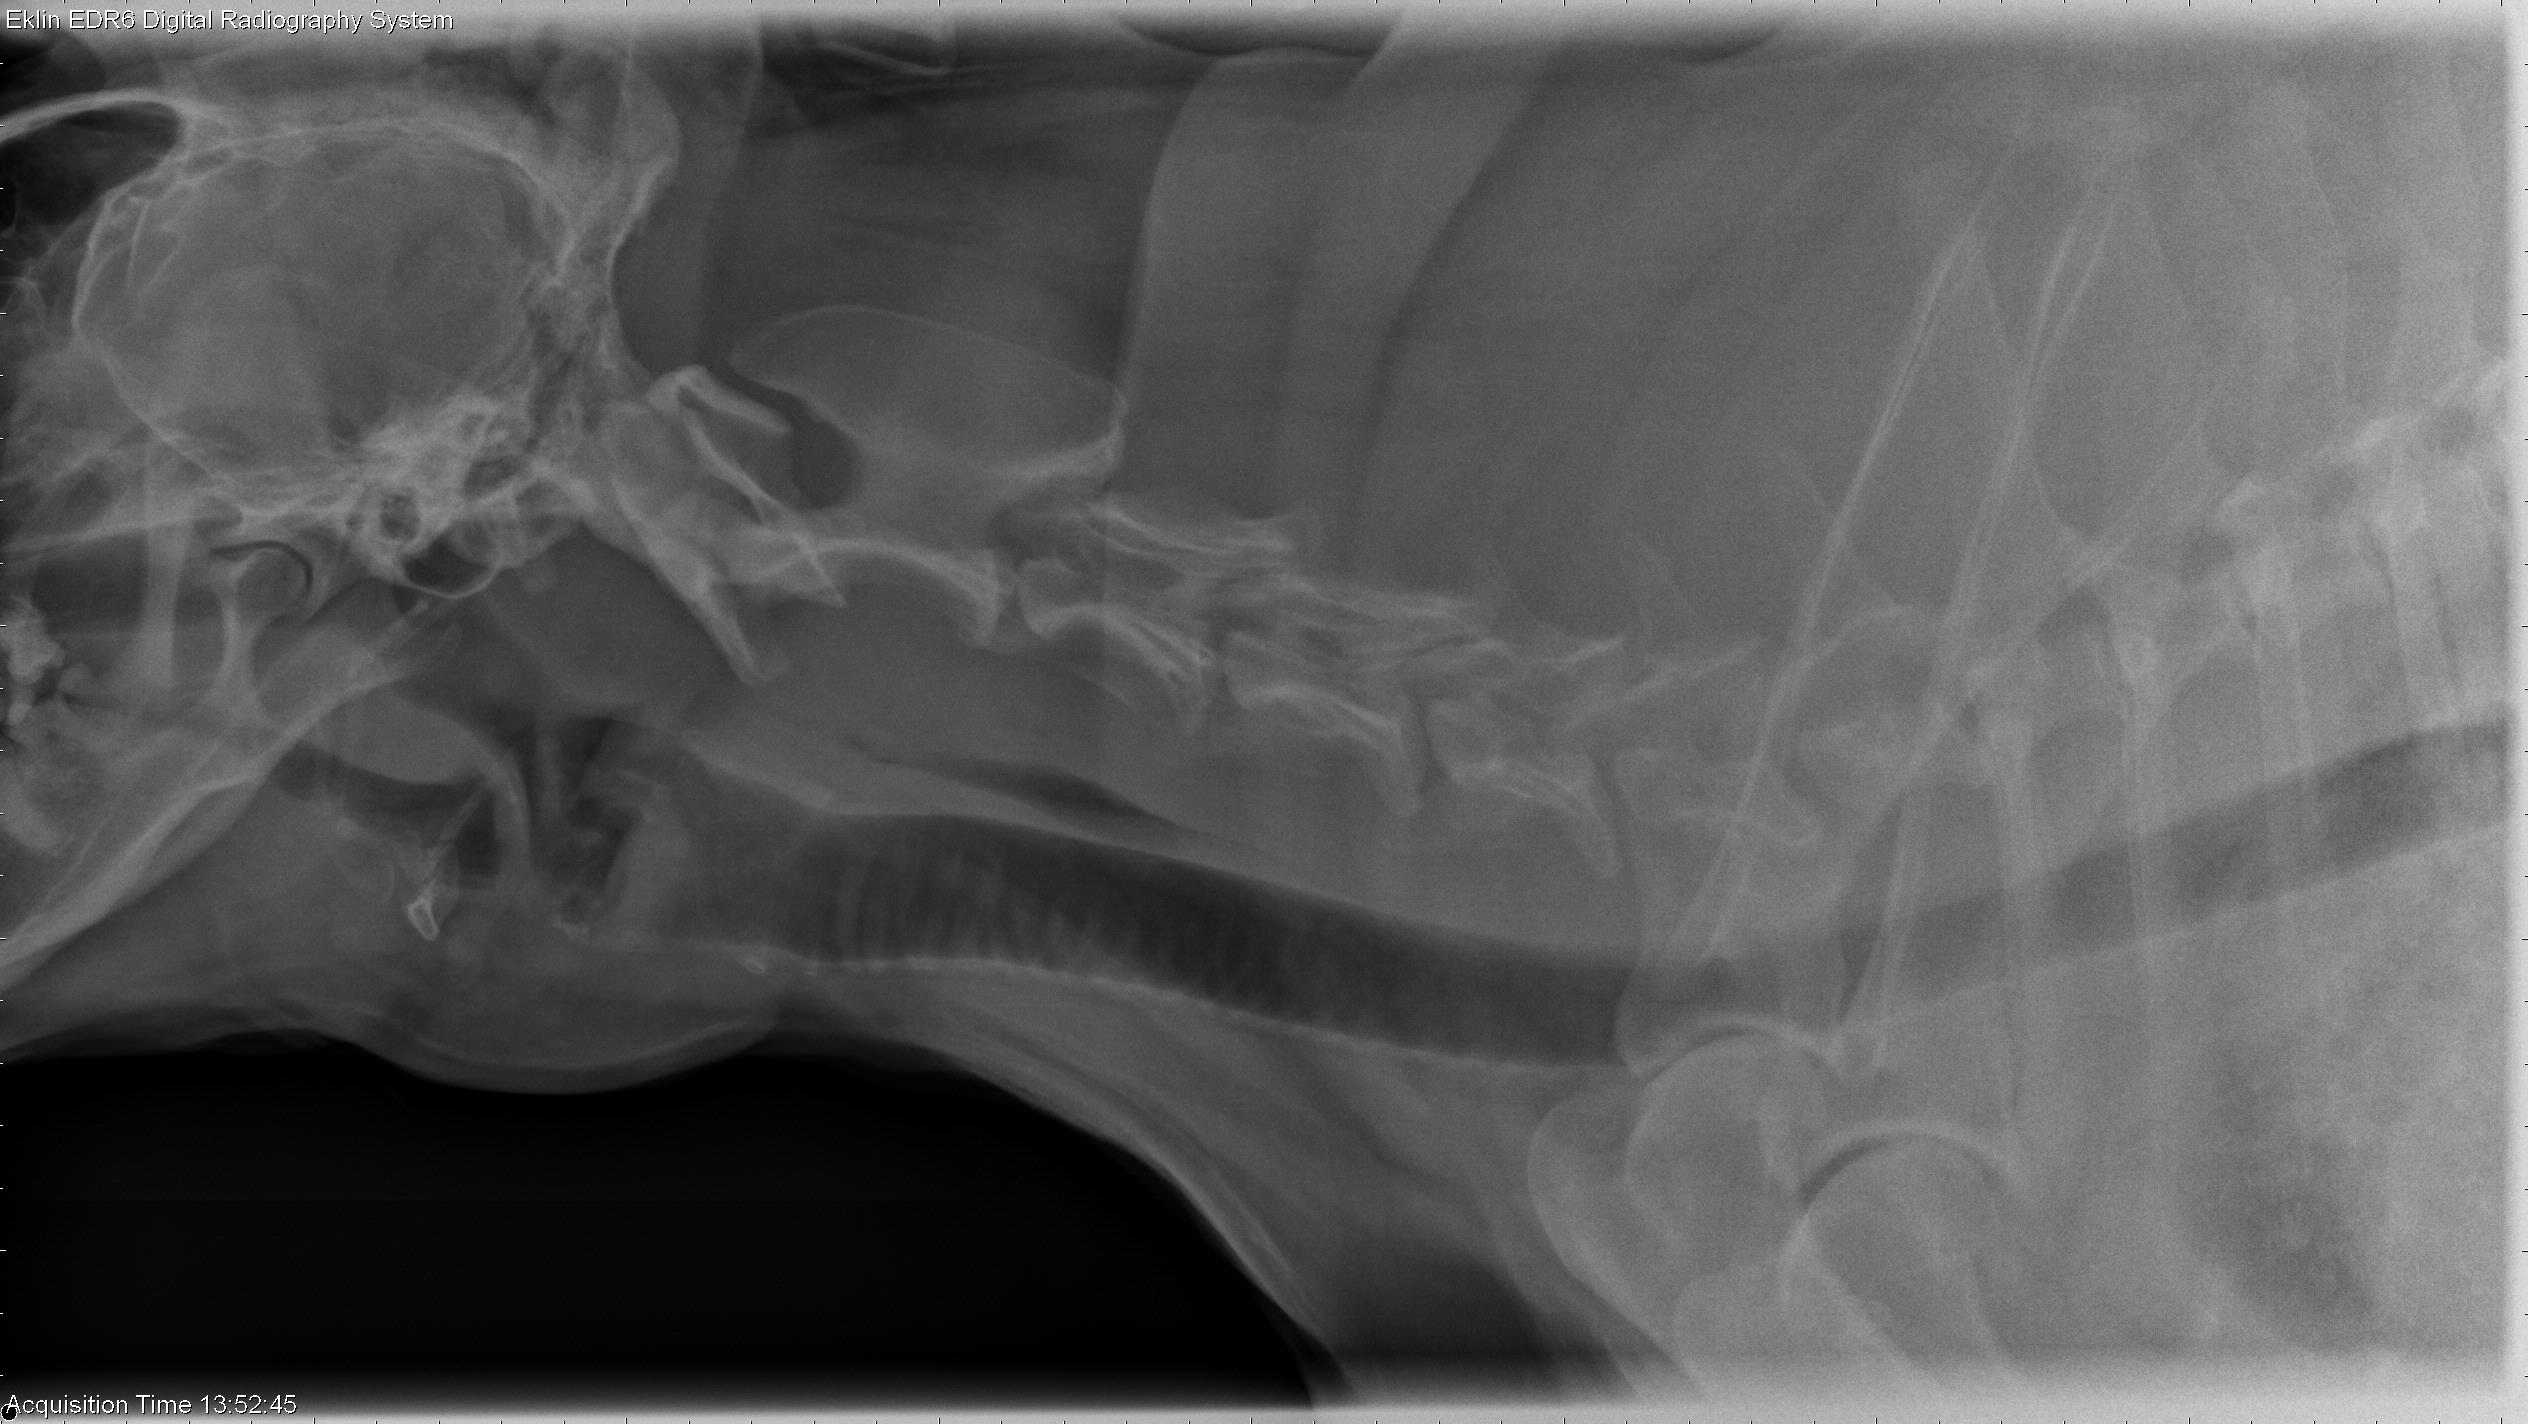

12 year old Labrador Retriever

from www.veterinaryradiology.net